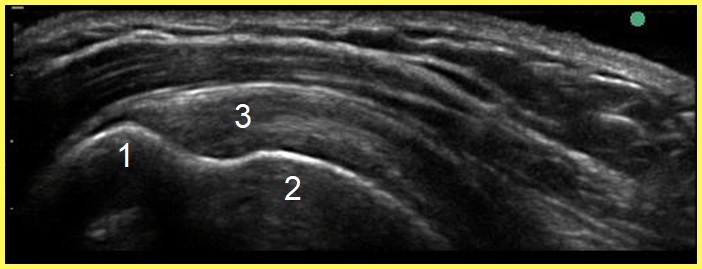

Image : Épaule : Anatomie du trochiter 2, Profil osseux longitudinal

Trochiter antérieur

1. Tendon supra-épineux

2. Empreinte du trochiter/Insertion du tendon